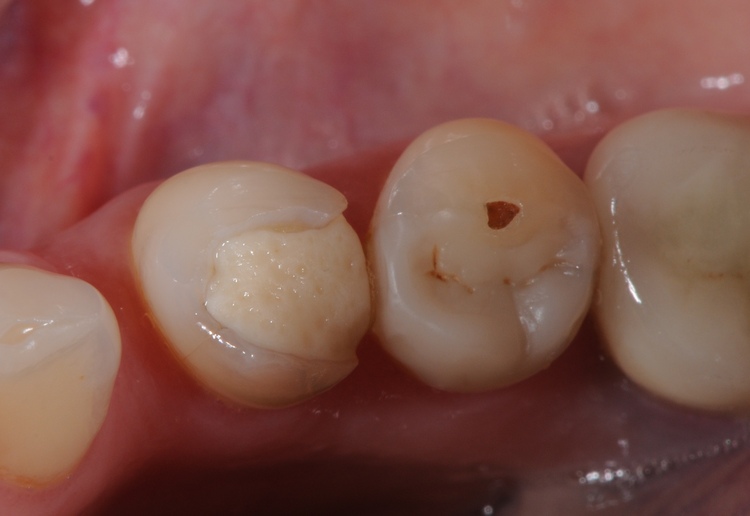

4. Discoloration or Dark Lines Around the Filling

Dark lines, gray shadows, or brown/black staining around the edges of a filling often indicate leakage or recurrent decay. When the seal between the filling and tooth weakens, bacteria and pigments can penetrate the margins.

Discoloration around older restorations is a common sign that decay may be developing underneath. Even if there is no pain yet, visible staining at the margins should prompt a dental evaluation to prevent deeper progression.